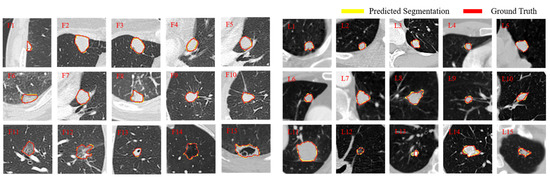

5.3. Qualitative Analysis